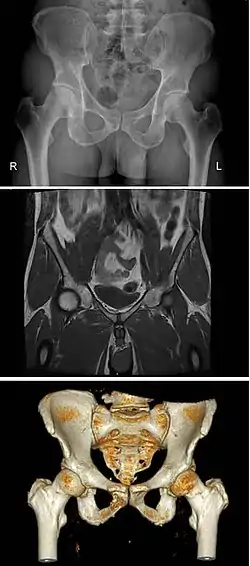

Pelvic bone

2–4. Hip bone (os coxae)

1. Sacrum (os sacrum), 2. Ilium (os ilium), 3. Ischium (os ischii)

4. Pubic bone (os pubis) (4a. corpus, 4b. ramus superior, 4c. ramus inferior, 4d. tuberculum pubicum)

5. Pubic symphysis, 6. Acetabulum (of the hip joint), 7. Obturator foramen, 8. Coccyx/tailbone (os coccygis)

Dotted. Linea terminalis of the pelvic brim.

The pelvic skeleton is formed posteriorly (in the area of the back), by the sacrum and the coccyx and laterally and anteriorly (forward and to the sides), by a pair of hip bones. Each hip bone consists of three sections: ilium, ischium, and pubis. During childhood, these sections are separate bones, joined by the triradiate cartilage. During puberty, they fuse together to form a single bone.